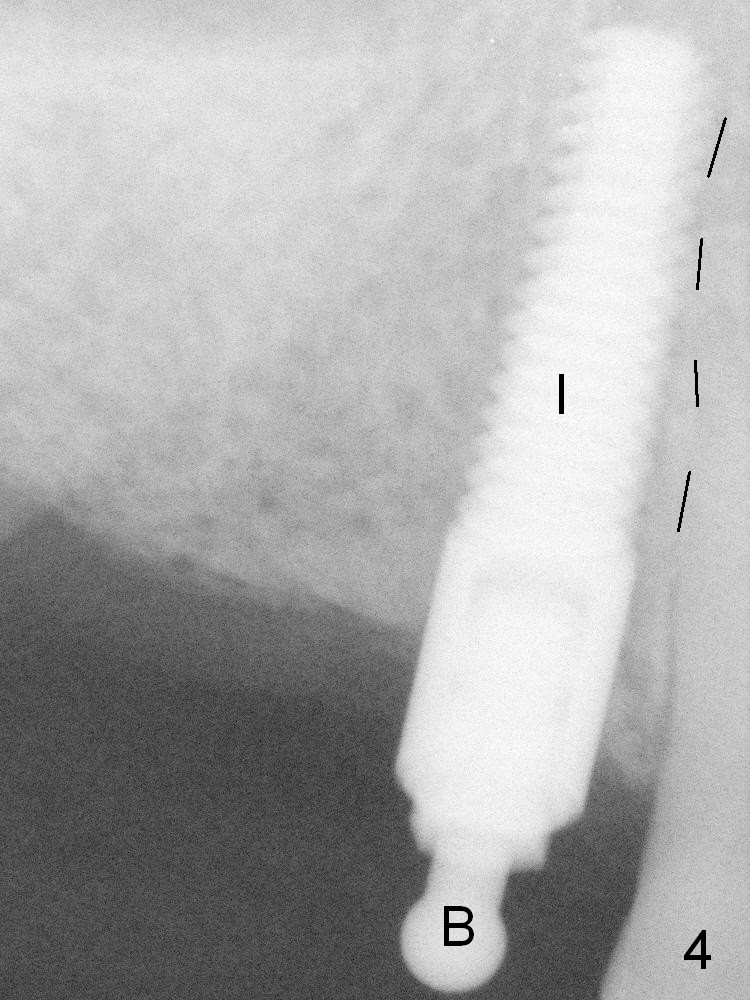

After initial osteotomy at the site of #6 with a 2 mm pilot drill at 11 mm, a parallel pin is inserted (Fig.1). It appears close to the neighboring root (dashed line), although it does not look so close clinically. When the parallel pin is removed (Fig.2 black area), the osteotomy is moved distally (red area) with a Lindamann bur. Then the osteotomy is deepened and enlarged (Fig.3 green area). When a 4x17 mm tissue-level implant is placed (Fig.4 I), a ball abutment (A) is inserted without enough clearance. The clearance with a ball abutment at the site of #3 is also not sufficient. It appears that crowns have to be fabricated prior to fabrication of the upper removable partial denture.